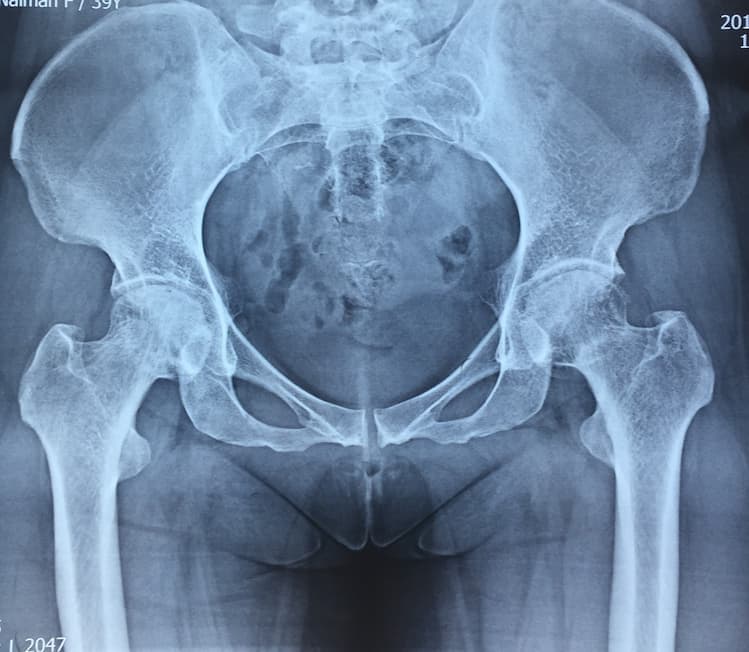

Түнхний үений төрөлхийн мултрал дутуу хөгжилтэй өвчтөний мэс заслын өмнөх болон дараах рентген зураг

Түнхний үе бүтэн солих мэс засал (THA) image3Түнхний үе бүтэн солих мэс засал (THA) image4